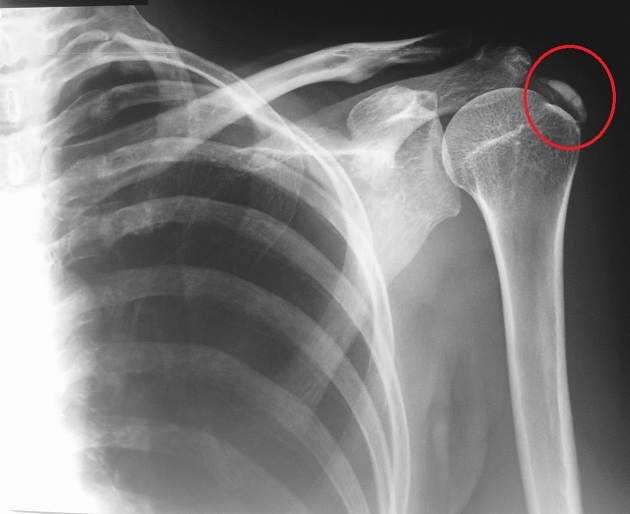

- Ακτινογραφία ώμου (αναδεικνύει τις ασβεστοποιήσεις)